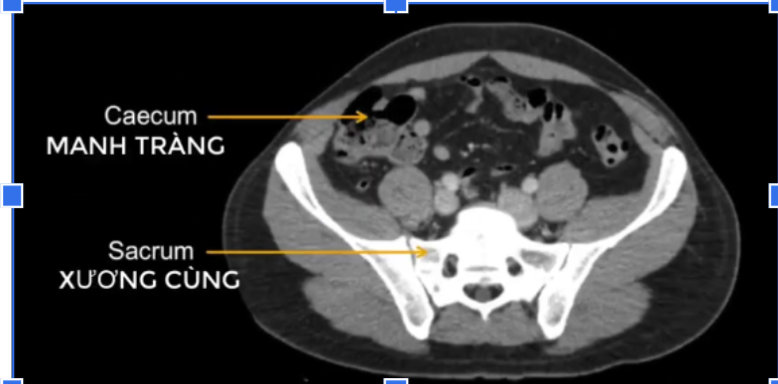

manh tràng? x cùng?